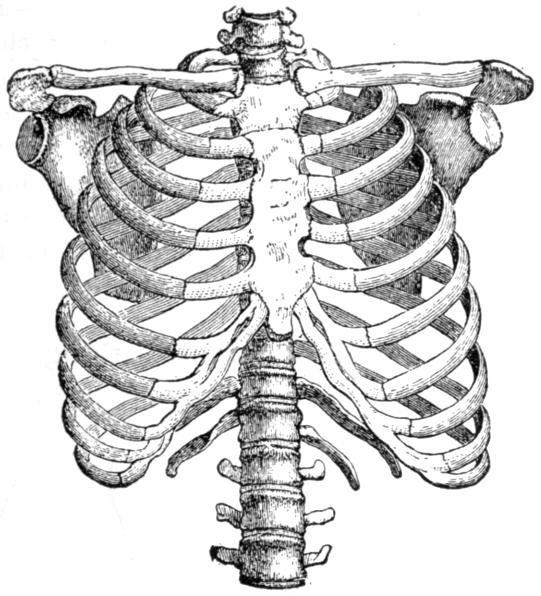

| III. | The Skeleton | H 28 |

| IV. | The Muscles | H 39 |